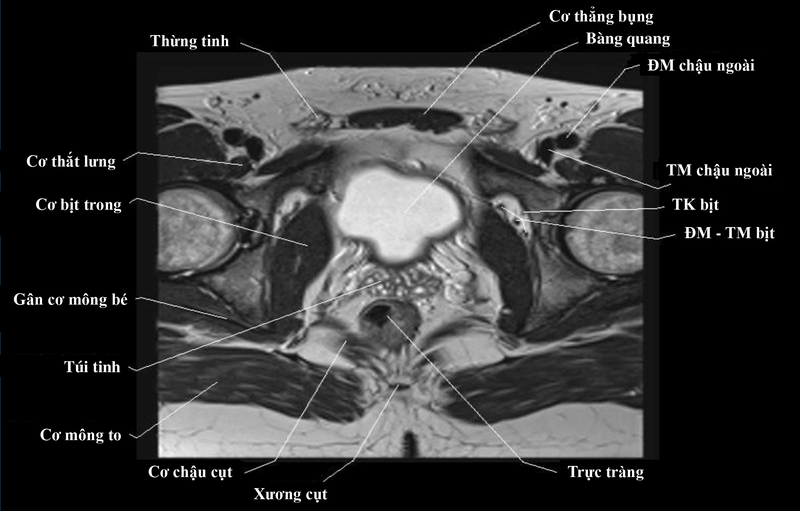

Chụp MRI tiểu khung là một phương pháp chụp và chẩn đoán hình ảnh an toàn và hiện đang được sử dụng rộng rãi trong các cơ sở khám chữa bệnh. Phương pháp này cung cấp hình ảnh chi tiết về các cơ quan, cấu trúc bên trong cơ thể, không chỉ giúp phát hiện, tầm soát, chẩn đoán các bệnh lý nguy hiểm mà còn là cơ sở để bác sĩ xây dựng kế hoạch điều trị hiệu quả cho người bệnh.

Chụp MRI còn được gọi là chụp cộng hưởng từ, là phương pháp sử dụng từ trường lớn, sóng vô tuyến và xử lý mạnh mẽ của máy tính để tạo ra hình ảnh chi tiết về các cơ quan trong cơ thể mà bạn muốn kiểm tra, chẳng hạn như: Hộp sọ, cột sống, bụng, xương chậu, phần mềm,... Dựa trên kết quả chụp MRI và thăm khám, xét nghiệm, bác sĩ có thể chẩn đoán tình trạng sức khỏe của bệnh nhân và lên phác đồ điều trị bệnh. Không giống như chụp X-quang và chụp cắt lớp vi tính (CT), chụp MRI không sử dụng bức xạ ion hóa có hại của tia X.

Chụp MRI tiểu khung hay còn gọi là vùng chậu được sử dụng để phát hiện các dấu hiệu bệnh lý và sự phát triển của ung thư vùng chậu trong quá trình điều trị. Sau khi chụp MRI, bác sĩ có thể phân loại và đánh giá các giai đoạn ung thư của bạn, cho phép bạn lập kế hoạch điều trị hiệu quả cho từng giai đoạn của bệnh.

Ngoài ra, chụp MRI tiểu khung có thể giúp phát hiện ung thư ở các cơ quan lân cận như bàng quang và tuyến tiền liệt ở nam giới, buồng trứng và tử cung ở phụ nữ, hạch bạch huyết, đại tràng và ruột non, cấu trúc của xương chậu,...